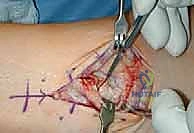

2. الوصول الجراحي الدقيق

يقوم الدكتور هطيف بعمل شق جراحي دقيق في الجزء الأمامي من الكاحل. بفضل خبرته في الجراحة الميكروسكوبية، يتم إبعاد الأوتار والأعصاب والأوعية الدموية بحذر شديد لحمايتها من أي ضرر.